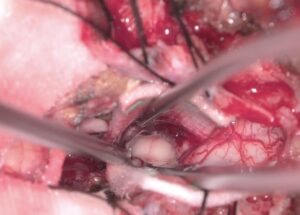

260324 78歳男性 大型下垂体腺腫を外視鏡+内視鏡の複合手術を行いました。

視力視野障害が進行する太型下垂体腺腫に対して複合手術を行いました。

二面のモニターをうまく配置して経鼻と開頭の二歩行から腫瘍を摘出し、術後悪化なく腫瘍摘出ができました。